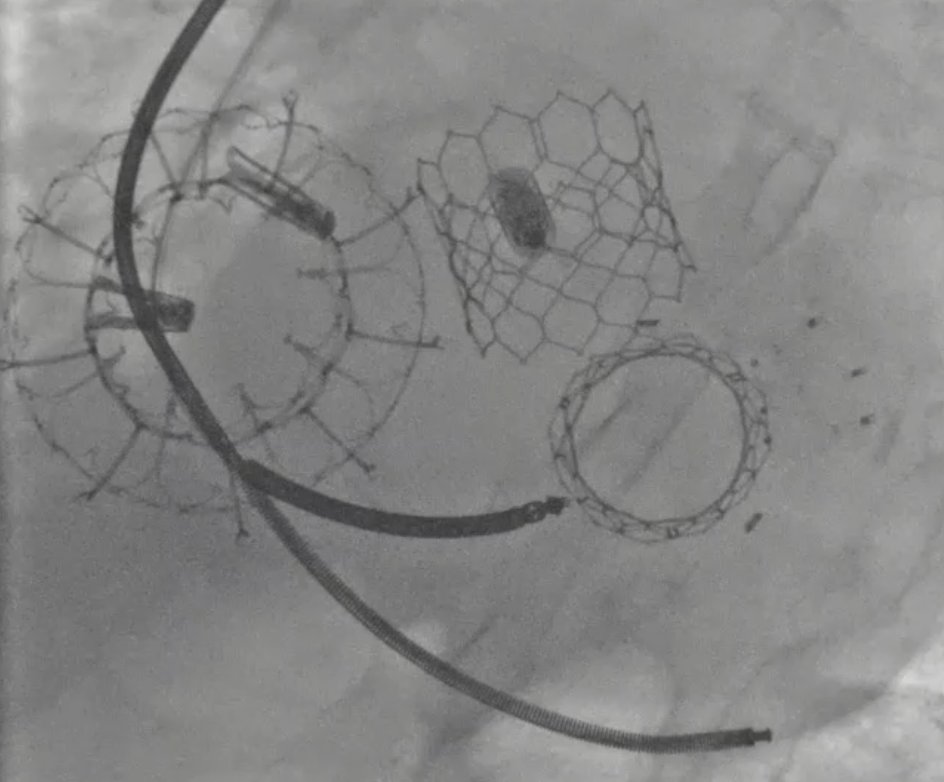

First EVOQUE transcatheter tricuspid valve replacement (56 mm) in Israel at Sheba Medical Center.

80-year-old patient post RV lead extraction and leadless pacemaker, successfully treated for severe TR — no residual TR and doing great the next day. @PCRonline @EdwardsLifesci